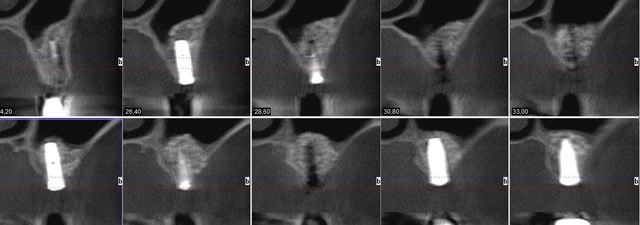

pour illustrer cette utilisation du bioactys, voici un cas (ce matin, mise en focntion des implants à 7 mois post_op)

Coupes pr  op inlfb8 - Eugenol